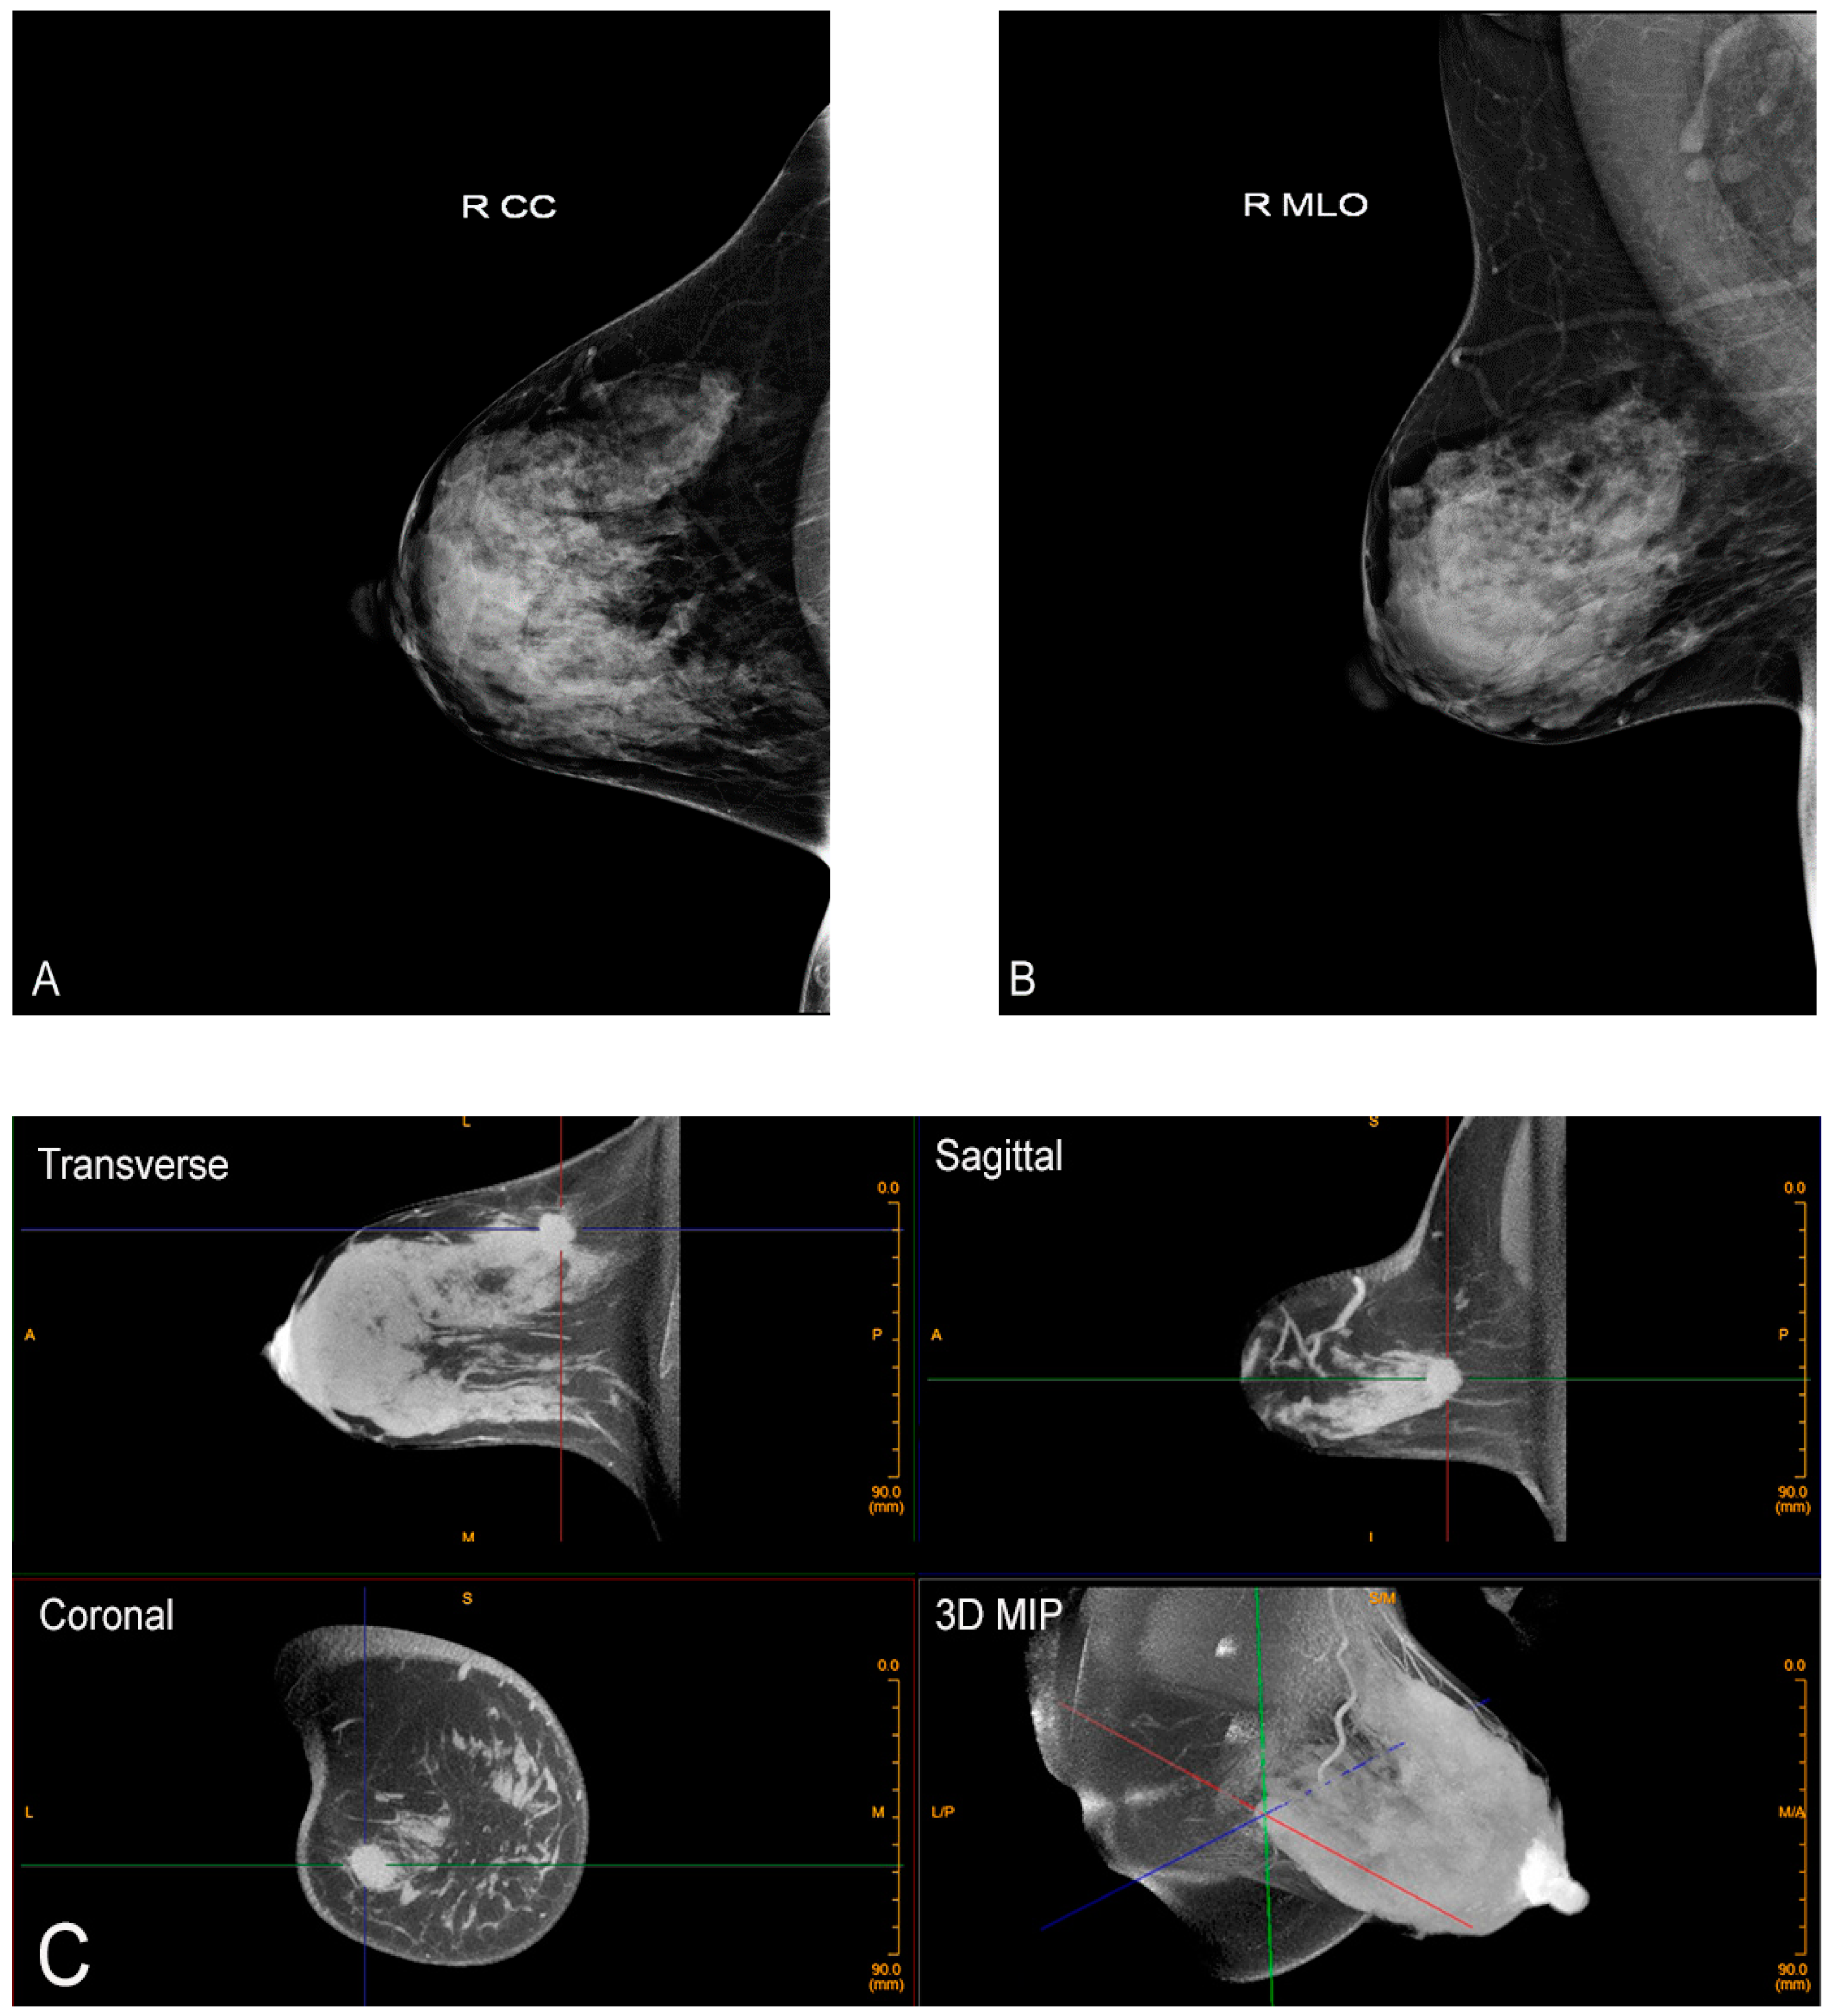

2. Cone-Beam Breast Computed Tomography